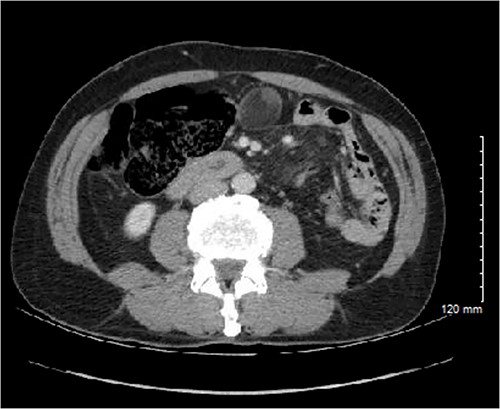

The specimen contained a 4.5 × 3.5 × 2.6 cm soft tissue mass with intact serosal covering encased within the pericolonic adipose tissue (Fig. 4). The specimen had no connection to the muscular wall of the colon, though there was a ball of sebaceous material and hair. Importantly, no solid areas were identified in this cyst, and no other tissue types were identified microscopically besides the squamous epithelial lining within a thin wall of loose connective tissue. Further testing, including histochemical staining and immunohistochemistry, revealed mature cystic teratoma in the pericolic fat with uninvolved margins (Fig. 5).

Gross pathology specimen showing a smooth walled cyst to the right of opened colon. The cyst was encased in fat and had no connection to the wall of the colon. There are no solid areas identified in the cyst. Separately, there is a ball of sebaceous material and hairs.